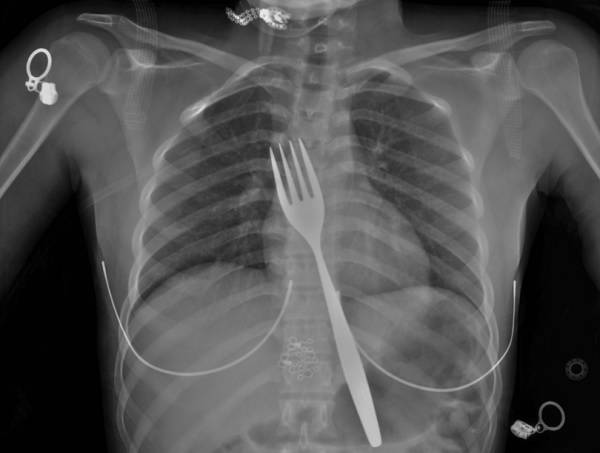

"이게 말이 돼?"… 실수로 포크 삼킨 20대 여성, 제거는 어떻게?

터키 아드난 멘데레스대 의대 외과 의료진은 22세 시리아 여성 A씨가 윗배 통증과 메스꺼움을 호소하며 병원 응급실을 찾았다고 밝혔다. A씨는 아이들과 놀다가 실수로 포크를 삼켰다고 했다. 의료지이 흉부 엑스레이를 찍어보니 실제 A씨 뱃속에 포크가 있는 게 보였다. 식도에 포크 윗부분이 있고, 손잡이 부분이 위 안쪽으로 뻗어 있는 모습이 확인됐다. 다행히 식도나 주변 장기에 구멍이 나는 등의 손상은 없는 것으로 추정됐다. 의료진은 내시경을 통해 제거하면 포크 뾰족한 부위에 긁히며 식도 등에 손상이 생길 우려가 있다고 판단, 배를 열어 꺼내는 개복술을 시행하기로 했다. 의료진은 윗배 중앙선을 4cm 절개했고, 수술은 70분간 진행됐다. 의료진은 "위 장막 쪽에 포크 손잡이가 보여 조심스럽게 잡고 빼냈다"고 했다. 다행히 수술은 성공적으로 끝났고 이후 A씨는 입으로 음식을 먹는 데 문제가 없었다. 이후 외래 추적 관찰에서 특별한 이상 증상이나 합병증이 없다고 확인됐다.

아드난 멘데레스대 의대 외과 의료진은 "과거에 플라스틱 포크를 삼켜 장에 구멍이 뚫리고 복막에 염증이 발생한 사례가 보고된 바 있다"며 "숟가락, 칼을 삼킨 환자 사례도 있었다"고 했다. 이어 "이물질 삼킴 사고의 약 1%에서 수술적 개입이 필요하다"며 "포크 삼킴 사례가 점차 많이 보고되고 있는데, 내시경으로 안전하게 제거할 수 없는 경우 개복술이나 배에 작은 구멍을 뚫어 시행하는 복강경 수술을 통한 외과적 개입을 고려해야 한다"고 설명했다.

이 사례는 '큐레우스' 저널에 지난 28일 게재됐다.